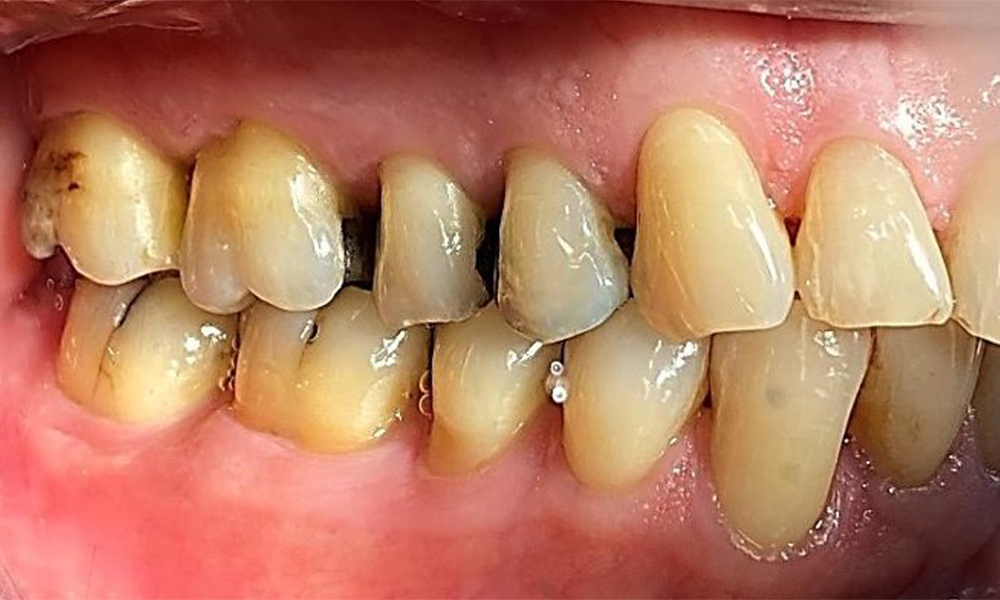

Lateralansicht rechts. Verlust der interdentalen Papillen. © Dr. R. Krapf

Abb. 3 Lateralansicht rechts. Verlust der interdentalen Papillen. © Dr. R. Krapf

Parodontaler Befund

Der Patient hat eine Parodontitis Stadium II, Grad B (5). Die klinischen Sondierungstiefen liegen mit 1-3mm im physiologischen Bereich. Lokalisierte Sondierungstiefen finden sich an 17 und 27 jeweils mesiopalatinal mit 5mm. Es liegen generalisierte Rezessionen von 1-3mm vor mit partiellem Verlust der Interdentalpapillen (Abb. 2, Abb. 3, Abb. 4)